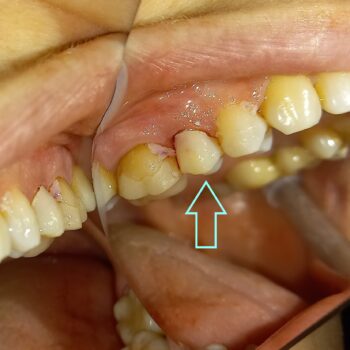

Η σημασία της προσωρινής αποκατάστασης κατά τη διάρκεια προσθετικής εργασίας